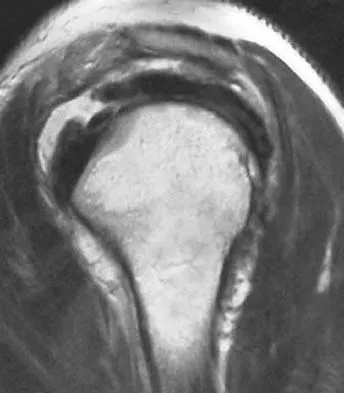

A 36-year-old woman has pain and swelling of the anterior arm after undergoing arthroscopic shoulder surgery 8 months ago. At the time of the procedure, extensive debridement and synovectomy of the anterior aspect of the joint was performed to remove scar tissue that had formed after an open rotator cuff repair. Examination reveals a golf ball-sized swelling just lateral to the coracoid. The area is not warm and shows no other signs of infection. An MRI scan is shown in Figure 1. Management should now consist of